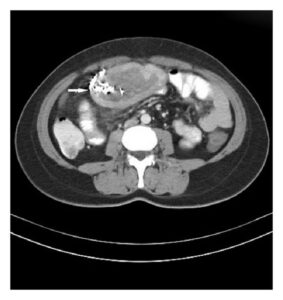

CT scan (often shows spongiform mass, internal gas bubbles, “whirl” or mottled pattern)

Know that diagnosis is often delayed, and imaging features (CT with spongiform pattern) are helpful.